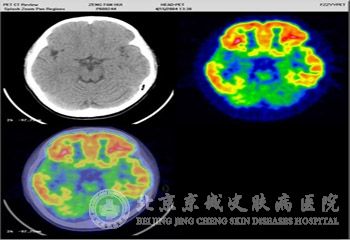

结节性硬化症在病发时的神经胶质增生性硬化结节的分布位置主要位于大脑皮质、白质基底节和室管膜下,而且经常会伴有钙质沉积,也会出现异位症以及血管增生等病症。

结节性硬化症在脑部的主要病理变化表现为在大脑皮质中有很多硬实的结节,同时在白质内也会出现异位*团,脑室壁内会有小结节,在其中皮质结节的数目不一,在1至40之间浮动,数量较多的就是额叶部位。此病的病发部位也不固定,有时也会发生在丘脑、基底节小脑脑干和脊髓等部位,而且结节的大小不一,有的直径甚至可超过3cm,一般表现为巨脑回畸形。